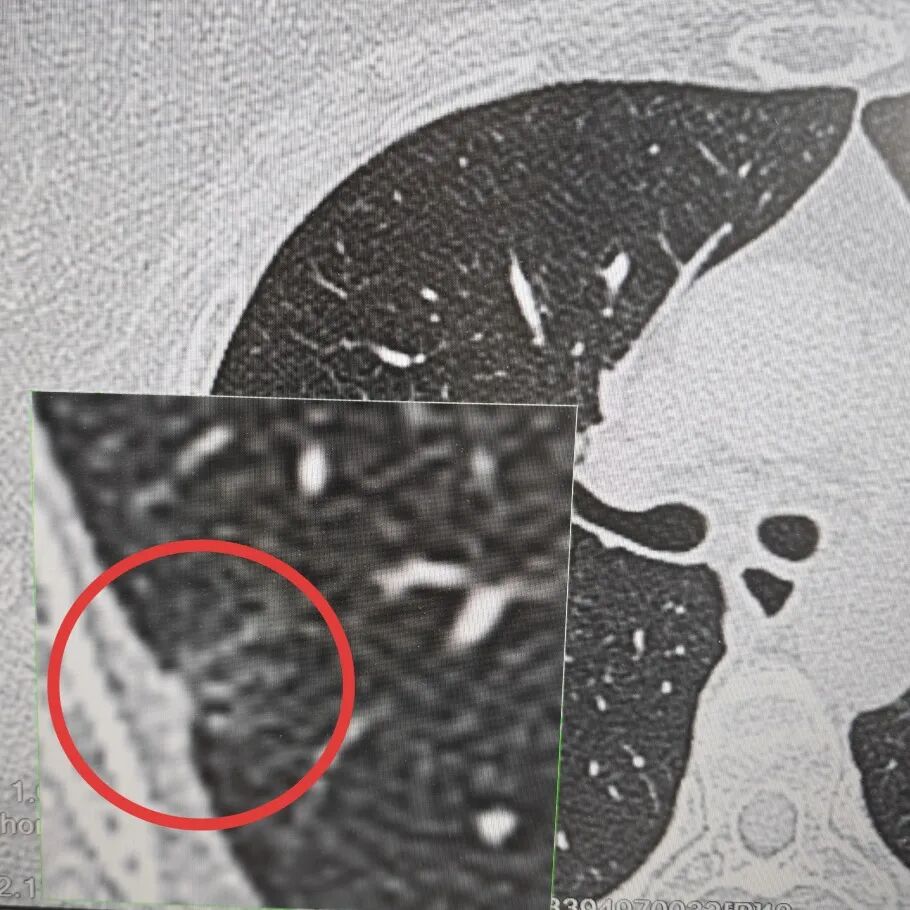

内容提要 >> “最初我们因肺结节多方求医,北京专家也曾倾向于良性病变,让我们一度放下心来。但葫芦岛二院孙振主任,凭借精湛的专业技术,敏锐地察觉出结节存在恶性风险(右肺上叶部分实性结节与右肺上叶磨玻璃结节),果断建议我们尽快手术治疗,为我们争取到了最宝贵的治疗时机……” 近日,市二院胸外科孙振教授团队收到一封情真意切的感谢信,这背后,是孙振教授靠着40年的临床经验,从看似“安全”的结节中,敏锐地发现了真正的风险。 半年前,患者体检时发现右肺上叶有个结节。家人不放心,专程去了北京,得到的诊断是“良性”。听到这个结果,全家人总算松了口气,决定先观察,定期复查。 今年1月,患者于我院复查胸部高分辨率CT(HRCT),结果显示:双肺多发大小不等结节,右肺上叶后段部分实性结节,大小约11mm×9mm,其内可见支气管影,周围伴有血管集束征;右肺上叶后段另见一枚约9mm×7mm的磨玻璃小结节。 孙振教授把患者历次影像资料反复对比,凭借几十年在胸外科一线积累的经验,敏锐判断这些结节恶性风险较高,建议尽快手术。他把自己的判断一五一十讲给患者和家人听,这份底气十足的诊断,最终让一家人选择留下来,在市二院接受手术。 手术由孙振教授主刀。术前先在CT引导下精准定位结节,术中采用胸腔镜微创技术进行肺段切除。术中冰冻病理结果很快出来:结节1是原位癌,结节2是浸润性腺癌,且结节2离切缘较近。孙振教授当即调整手术方案,改行右肺上叶切除,最大程度降低术后复发风险。 原位癌 浸润性腺癌 术后,在医护团队精心照护下,患者恢复顺利,仅5天便康复出院。一家人感激不尽,这才有了那封情真意切的感谢信和那面写有“妙手仁心医术高,德术双馨暖人心”的锦旗。 “……这无疑是最理想的手术结果。这份成功的背后,是您深厚的医学功底、严谨的诊疗态度,以及对患者生命高度负责的医者仁心。”一字一句,饱含着对孙振教授、马遇川医生、郭晨光护士长及胸外科全体医护人员的深深谢意与由衷认可,也生动诠释了“大病不离葫”这一民生承诺背后,最温暖、最坚实的力量。 孙振教授从事胸外科临床工作近40年,长期专注于肺结节、食管癌、肺癌等胸部疾病的精准诊疗,尤其在复杂食管癌根治术、胸腔镜微创手术等高端技术领域经验丰富,手术成功率高,患者长期生存质量显著提升。他用一双“火眼金睛”,为滨城百姓的肺部健康筑牢了坚实防线。 孙振 主任医师 三级教授 ·葫芦岛市第二人民医院胸外科主任、肺结节诊治中心主任 ·中国医科大学客座教授 ·原央企总医院著名胸外科专家 ·辽宁省医学会胸外科委员 ·辽宁省抗癌协会肺癌专业委员会委员 ·辽宁省细胞生物学学会食管癌专业委员会理事 ·主持多项科研成果,获科技成果奖、科技进步奖、国家专科奖项 医学成就:从事胸外科临床工作近40年,担任胸外科首席专家及科室主任20余年,是我省胸外科领军人物,推动肺癌、食管癌等胸部肿瘤外科的规范化诊疗,在央企总医院牵头成立了肺结节诊疗中心,率先开展CT引导下肺内小结节定位切除,既确切完整切除肺内小结节,又降低肺功能损害。 专业特色:擅长肺癌、食管癌的外科手术和综合治疗,在各类高难度胸外伤手术治疗、胸腔镜微创手术、胸腺瘤手术及复杂并发症处理方面具有高深造诣,尤其擅长肺癌早期诊断,胸部小结节CT早期肺癌的鉴别等。完成各类高难度胸外科手术5000余例,其中微创手术占比达90%,治愈率达98%,多项业务填补省内空白。 开展的高难手术包括:胸腔镜肺部结节微创手术、肺癌根治术、食管癌根治术、各种纵隔肿瘤切除术、胸骨后甲状腺手术及胸部复合性外伤的抢救手术等。 出诊时间:每周一、周二全天 出诊地点:门诊二楼著名专家诊区 咨询热线:16604299397